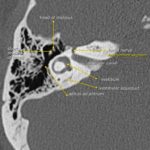

Giải phẫu CT Tai & Xương đá